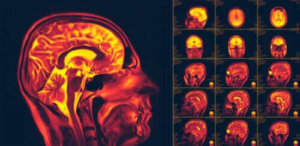

Neuroplasticitet i hjernen, også kendt som cerebral plasticitet, er en af de mest nylige opdagelser om den menneskelige krop. Det er hjernens evne til at ændre og tilpasse sig ny adfærd eller oplevelser.

Neuroplasticitet er neuroners evne til at regenerere. De gør dette både anatomisk og funktionelt. Faktisk er det en proces, der involverer mange biokemiske og metaboliske reaktioner. Det betyder også, at det har et stort tilpasningspotentiale.

Neuroplasticitet henviser til den måde, hvorpå vores nervesystem danner nye forbindelser. Derudover gør det dette som svar på nye stimuli, information eller endda for at helbrede skader i gamle forbindelser.

Derefter begyndte de at udføre forskellige billeddannelses- og stimuleringstest for at vise, at neuroplasticitet eksisterer. Forskere forsker stadig i alle aspekter af dette fænomen.